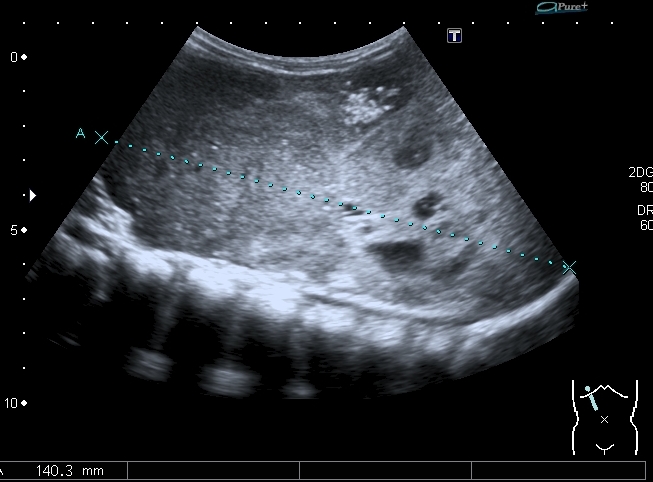

При УЗИ вся правая половина живота выполнена солидно - кистозным образованием больших размеров.

Правая почка нашлась в полости таза, верхним полюсом прилежала к образованию, но не была с ним связана.